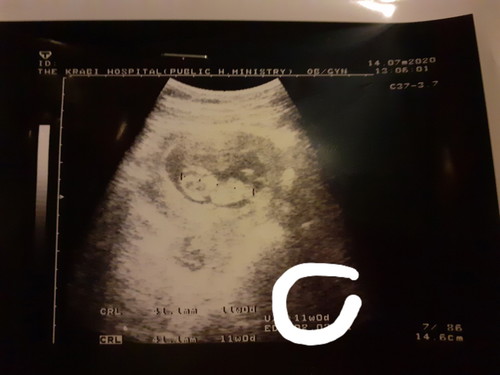

ขอถามหน่อยค่ะ ที่วงกลมในภาพที่ 11วีคใช่มั้ยค่ะ